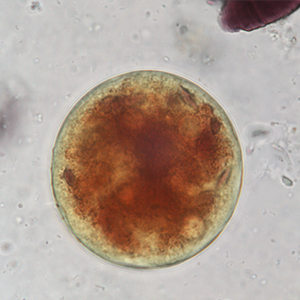

Le kyste est sphérique à ovoïde, à paroi épaisse, mesurant 50 à 100 μm de diamètre. Il présente un contenu granuleux, un macronucléus et micronucléus difficilement visibles (Strait et al., 2012). La coloration au Lugol permet de mettre en évidence certains organites qui apparaissent en brun sombre, de colorer la paroi en brun et l’intérieur du kyste en jaune.